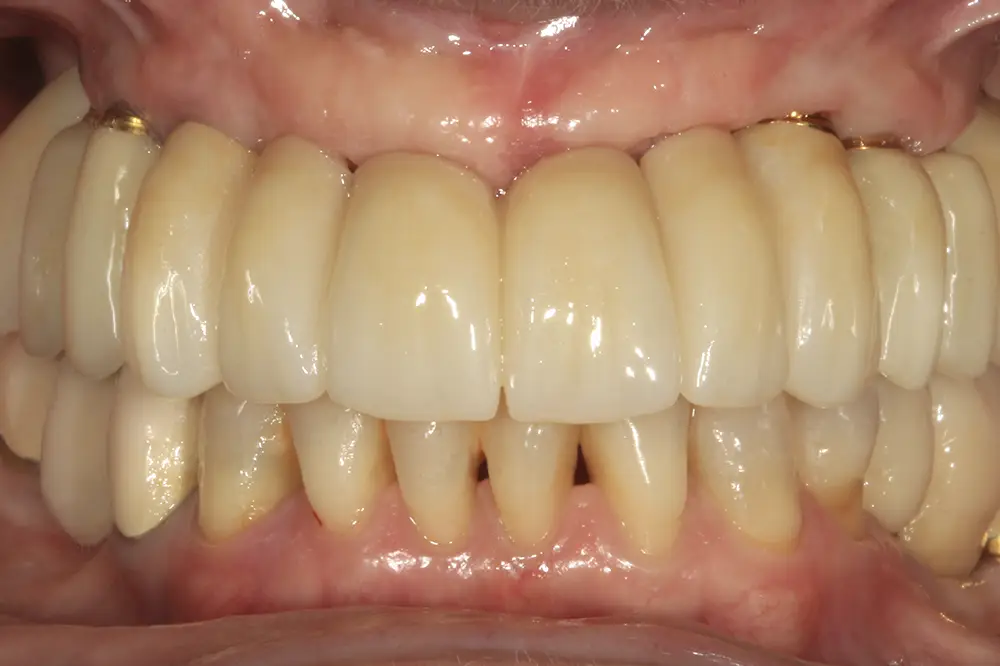

Presentamos el caso de una paciente de 67 años que acude a la consulta demandando tratamiento implantológico para el maxilar superior. Lleva varios años con prótesis removibles parciales, y ha ido perdiendo piezas de manera progresiva. Actualmente, tiene pocas piezas dentales remanentes y las que conserva tiene problemas de movilidad y dolor, por lo que consulta para poder rehabilitar con implantes la zona. En las imágenes iniciales podemos observar el estado de las prótesis removibles y los dientes naturales presentes (figs. 1-4)

Figs. 1-4. Imágenes iniciales de la paciente, donde observamos el estado de la prótesis removible que porta la paciente frontal y lateralmente, así como los dientes remanentes.